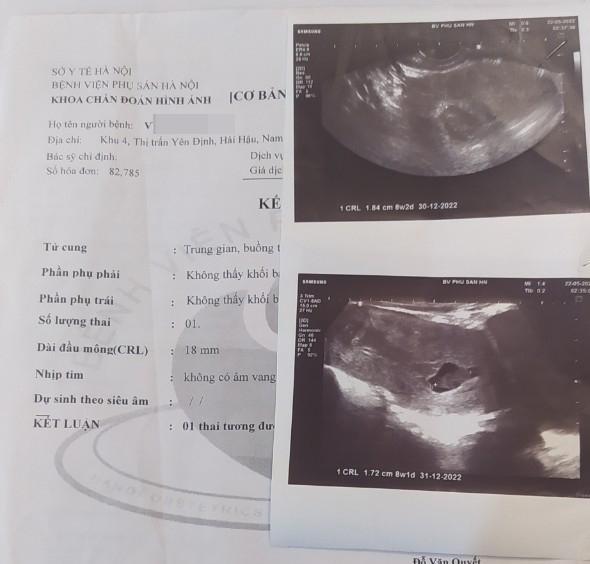

Hình ảnh siêu âm tim thai

Ghi nhận của Trí Thức Trẻ, theo kết quả siêu âm, bác sĩ kết luận chị Tr "1 thai tương đương 8 tuần 2 ngày, ngừng phát triển".